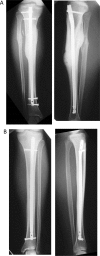

Posterior tibial stress fractures are more frequent than anterior tibial stress fractures, and they are considered to have a good prognosis for returning to sports; cases leading to a complete fracture are rare. A 17-year-old male involved in high school athletics middle-distance running had a 3-week history of pain with training. He was running up to 300 km/week on streets and cross-country in an even distribution. He had posterior tibial stress fractures, but despite the lower leg pain, he continued running. One year later, he was brought to the emergency department after having sustained an injury to the right lower leg while running in a middle-distance race; bilateral tibial stress fractures, with one side complete and the opposite side incomplete, had developed simultaneously. This relatively rare case of bilateral posterior stress fractures, with one side a complete fracture and the opposite side an incomplete fracture, that was treated surgically via exchange intramedullary nailing is reported. The patient could begin light jogging from 3 months after surgery and was without symptoms at 5 months after surgery. He could resume middle-distance racing after 1 year. Posterior tibial cortical fractures are more common and respond better to conservative treatment than anterior tibial stress fractures, and they are a common fracture type in runners. We believe that close, careful follow-up is necessary if patients continue excessive training.